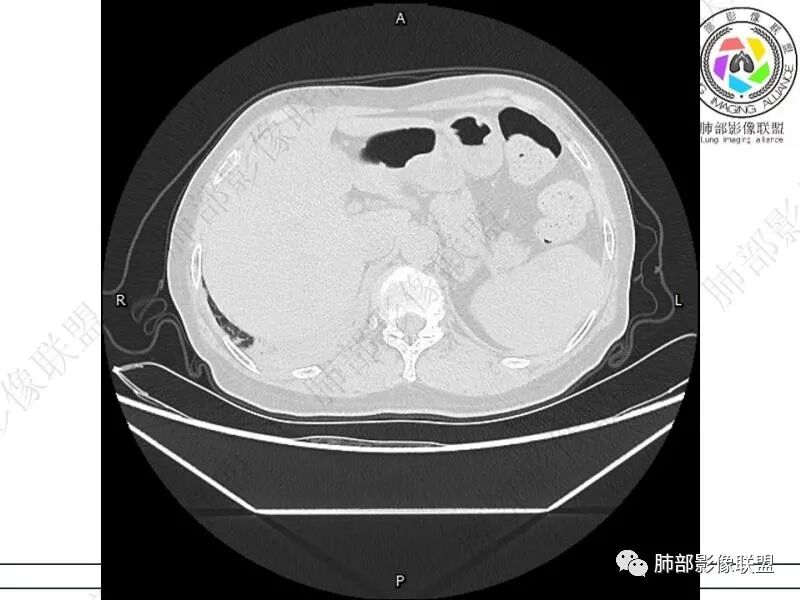

摘星空竹子:两肺胸膜下多发实性结节、磨玻璃影及实变影,短期复查病变有所进展,考虑感染性病变,隐球菌可能,患者有右半结肠癌手术史,转移不能除外。

简单:双肺及胸膜下多发小结节,双下肺胸膜下宽基底团块影,短期内病灶进展考虑炎性病变,隐球?患者ca术后,双肺小结节随诊除外转移

丽:双肺下叶胸膜下多发片状高密度影,边缘模糊不清,内可见支气管穿行,病变长轴平行于胸膜,考虑感染性病变,隐球菌

媛:肠癌术后,免疫力低下。两肺胸膜下结节及实变影,实变影长轴平行于胸膜,密度均匀,边界偏清,周围有晕征,短期复查进展,虽隐球菌荚膜抗原检测阴性,还是考虑隐球菌,鉴别OP

songml:老年女性,结肠癌术后,下腹隐痛。双肺胸膜下散在结节影,大小不一,下肺为著,肺野清晰,实变结节有强化,有毛毛征。考虑隐球菌感染。

谢加平:结肠癌术后史,两肺胸膜下多发结节及斑块实变病灶,实边边界平直征(亚急性和慢性病变过程),双肺下叶后基底段胸膜下为甚,与胸膜平行特点,见支气管充气征,边缘模糊的GG0,首诊2022年11月18日肺部CT,与治疗11月28日对比,病灶未吸收,双肺下叶胸膜下病灶有侧向融合特点,综合分析符合炎性肉芽肿,隐球菌感染。

老年女性,结肠癌术后。两下肺胸膜下为主片状实变,右下肺短期复查融合且病灶长轴平行于胸膜,实变内可见支气管充气征,边缘磨玻璃晕,另两肺内胸膜下散在数枚小结节状、楔形实性灶。考虑感染性病变,隐球菌可能,鉴别肺转移。

2.影像特征:双肺胸膜下多发实性结节、磨玻璃影及实变影,胸膜下优势分布、晕征、胸膜下脂肪间隙存在,部分病灶边界平直征,有侧向融合趋势。